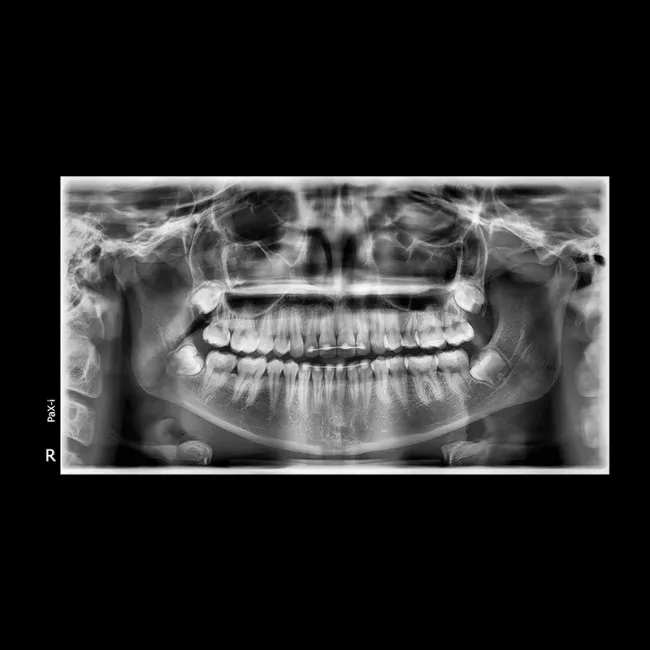

Полное изображение зубочелюстной системы Ортопантомограф предоставляет полную картину состояния зубов, челюстей, суставов и окружающих тканей. Это особенно полезно для выявления заболеваний, таких как кисты, опухоли, воспаления и повреждения челюстей.

Высокая точность и подробность снимков ОПТГ предоставляет детализированные изображения, что помогает врачу точно определить наличие заболеваний и планировать лечение. Снимки могут быть использованы для диагностики заболеваний, таких как кариес, пародонтит, а также для оценки состояния имплантатов и ортодонтических конструкций.

Планирование лечения Ортопантомограф используется для планирования лечения, например, при установке зубных имплантатов, ортодонтических аппаратов или при подготовке к хирургическим вмешательствам.

Диагностика заболеваний С помощью ОПТГ можно диагностировать такие заболевания, как кариес, пародонтоз, заболевания челюстных суставов, а также обнаружить опухоли и воспалительные процессы.

Контроль за состоянием после лечения Ортопантомографы также используются для мониторинга состояния пациентов после лечения, например, после удаления зуба, установки имплантатов или выполнения других процедур.